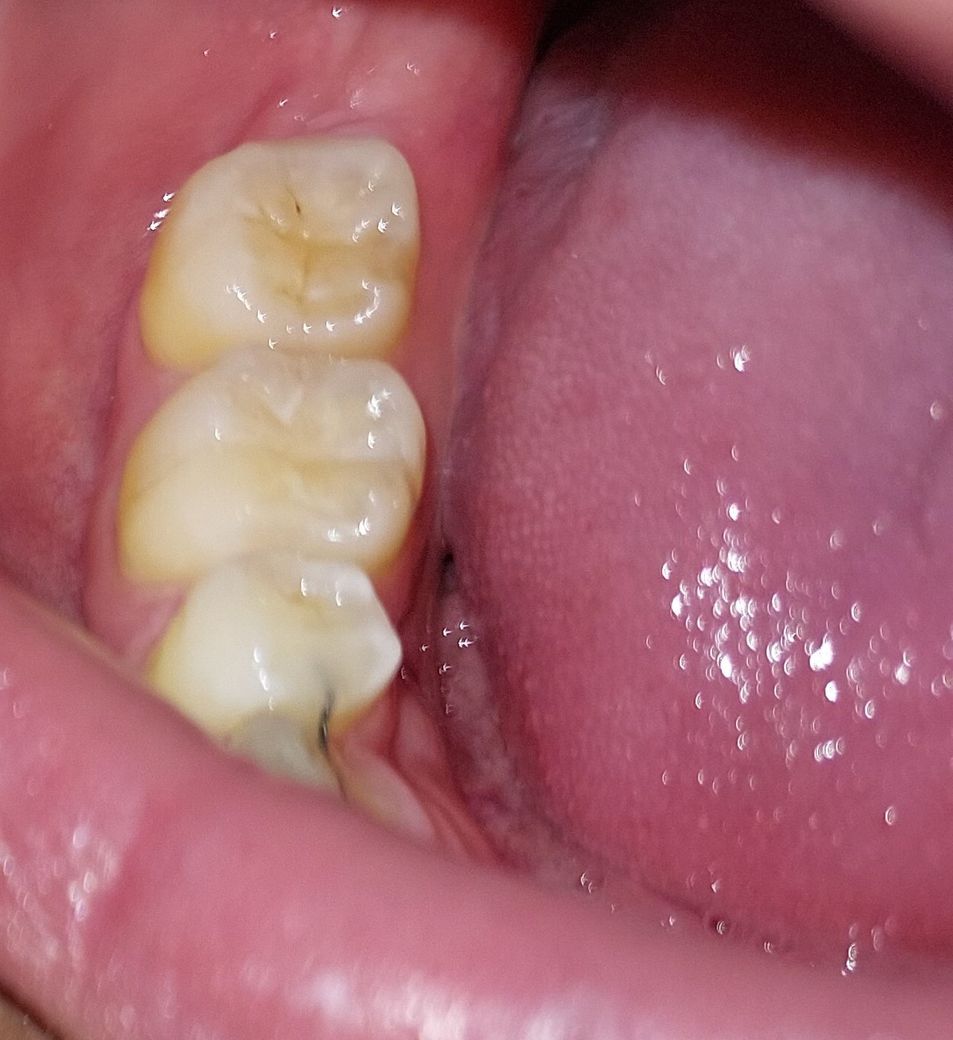

• 3번 째 사진

초기 충치가 잇는거 같으니 관리를 잘하시는게 좋을것같습니다. 정기적으로 치과를 다니시면서 관리를 받으세요.

두번째 사진이 현 상태라면 충치가 있더라도 깊은건 아닌듯 하고 치료보다는 주기적으로 체크하며 지켜보면 좋을 것 같습니다